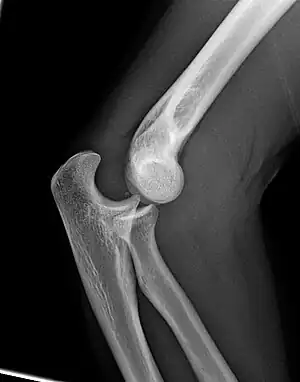

Right: AP X ray of a dislocated right elbow

Fractures

There are three bones at the elbow joint, and any combination of these bones may be involved in a fracture of the elbow. Patients who are able to fully extend their arm at the elbow are unlikely to have a fracture (98% certainty) and an X-ray is not required as long as an olecranon fracture is ruled out.[27] Acute fractures may not be easily visible on X-ray.[28]

Dislocation

Elbow dislocations constitute 10% to 25% of all injuries to the elbow. The elbow is one of the most commonly dislocated joints in the body, with an average annual incidence of acute dislocation of 6 per 100,000 persons.[30] Among injuries to the upper extremity, dislocation of the elbow is second only to a dislocated shoulder. A full dislocation of the elbow will require expert medical attention to re-align, and recovery can take approximately 6 weeks.